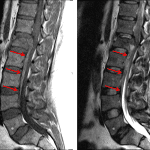

Indication: L1 burst fracture, lower extremity weakness

- Acute L1 vertebral body fracture with approximately 30% height loss and 6 mm bony retropulsion with resultant advanced spinal canal stenosis at this level

- Ventral epidural hematoma extending inferiorly from the L1 fracture to the level of the L4 superior endplate, measuring up to 5 mm in thickness with resultant advanced spinal canal stenosis at L1-L2, moderate spinal canal stenosis at L2-L3, and mild spinal canal stenosis at L3-L4

- Possible focal disruption of the anterior and posterior longitudinal ligaments at the level of L1

- T2/STIR signal hyperintensity in the T12-L1 interspinous ligament and in the supraspinous ligament at the level of T12 with focal disruption

- Prevertebral edema from L1-L2

- Epidural hematoma

- Ligamentous injury

Acute L1 vertebral body fracture with approximately 30% height loss and 6 mm bony retropulsion with resultant advanced spinal canal stenosis at this level. No abnormal signal of the conus.

Ventral epidural hematoma extending inferiorly from the L1 fracture to the level of the L4 superior endplate, measuring up to 5 mm in thickness with resultant advanced spinal canal stenosis at L1-L2, moderate spinal canal stenosis at L2-L3, and mild spinal canal stenosis at L3-L4.

Possible focal disruption of the anterior and posterior longitudinal ligaments at the level of L1. Interspinous and supraspinous ligament injury at T12-L1 with focal disruption of the supraspinous ligament adjacent to the T12 spinous process.